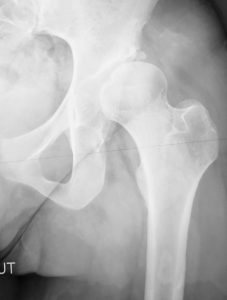

Lorsqu’un patient présente une dysplasie de la hanche, principalement cotyloïdienne (cf chapitre luxation congénitale de la hanche), la tête fémorale se décentre de son axe et l’articulation souffre. L’ostéotomie péri-acétabulaire est une intervention chirurgicale initialement décrite par R. Ganz en 1988, et qui a été modifiée pour être mini invasive à ce jour. Elle est conçue pour corriger les malformations de la hanche telles que l’insuffisance de couverture cotyloïdienne (dysplasie). Elle consiste à recentrer la tête fémorale en réaxant la cavité cotyloïdienne (au niveau du bassin).

Le diagnostic de dysplasie de hanche nécessite une évaluation précise de la morphologie de l’articulation de la hanche et du statut cartilagineux. Pour cela, le chirurgien, après un examen clinique indispensable, fera réaliser des radiographies complètes et un scanner du bassin, pour avoir des mesures précises sur la dysplasie. Il y est souvent associé un examen EOS permettant d’avoir des mesures de longueurs et d’axes au niveau des membres inférieurs.